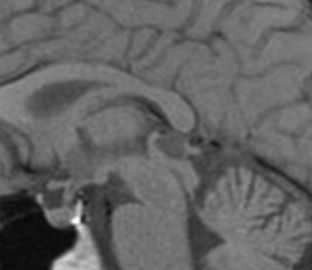

Киста кармана Ратке представляет собой редко встречающееся образование из остатков эмбриональной эктодермы (щель Ратке), расположенное между долями гипофиза. Выявляется в любом возрасте, но чаще в 50-60 лет. Клинические проявления связаны с масс-эффектом. При головного мозга выявляется небольшая (3-5 мм) киста с четким контуром, без отека вокруг, однородная по структуре. Сигнал зависит от содержимого. При серозном содержимом сигнал типично жидкостный, при мукоидном киста светлая на Т1-взвешенных МРТ. В редких случаях киста достигает больших размеров и даже выходит за пределы седла. Стенка кисты иногда усиливается при контрастировании.

МРТ головного мозга. Т2-взвешенная корональная МРТ. Киста кармана Ратке.

Киста кармана Ратке представляет собой редко встречающееся образование из остатков эмбриональной эктодермы (щель Ратке), расположенное между долями гипофиза. Выявляется в любом возрасте, но чаще в 50-60 лет. Клинические проявления связаны с масс-эффектом. При МРТ головного мозга выявляется небольшая (3-5мм) киста с четким контуром, без отека вокруг, однородная по структуре. Сигнал на МРТ головного мозга зависит от содержимого. При серозном содержимом сигнал типично жидкостный, при мукоидном киста светлая на Т1-взвешенных МРТ головного мозга. В 70-80% случаев внутри кисты выявляется неконирастирующийся узелок («пятно») - признак патогномоничный для кисты кармана Ратке. В редких случаях киста достигает больших размеров и даже выходит за пределы седла. Стенка кисты иногда усиливается при МРТ головного мозга с контрастированием. Дифференциальная диагностика при МРТ головного мозга должна проводиться с арахноидадьной и эпидермоидной кистами, тератомой, кистозной аденомой гипофиза и краниофарингиомой. Иногда при МРТ головного мозга киста кармана Ратке напоминает “пустое” турецкое седло. При маленьких размерах кисты ее на до дифференцировать на МРТ с микроаденомой гипофиза.

![Ratke cleft cyst]()

МРТ головного мозга. Т1-взвешенная сагиттальная МРТ. Киста кармана Ратке.